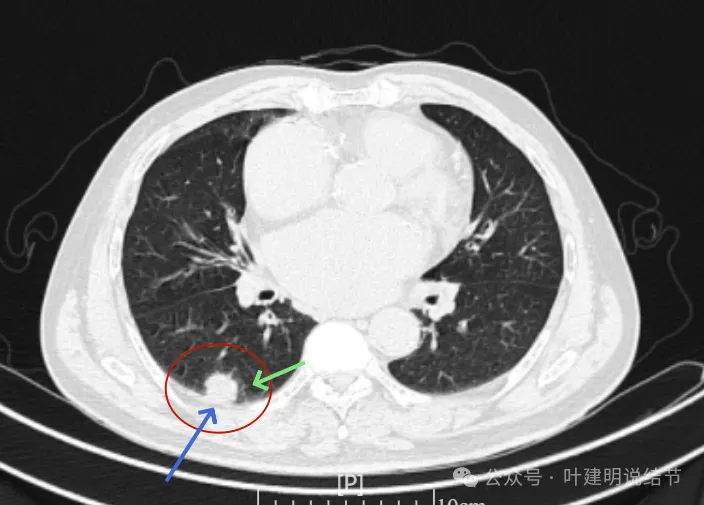

右上没有明显变化,仍考虑良性可能性大。

左下也考虑良性,与2022年无明显变化。

右下新增病灶,混合密度,整体轮廓较清,瘤肺边界欠清。

这是冠状位、矢状位与轴位的影像。